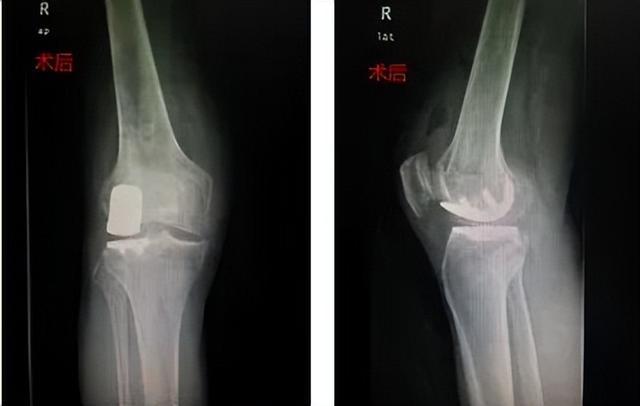

经过仔细评估,罗海恩主任团队决定为他实施一种相对微创的治疗方案——单髁置换术,手术仅60分钟便圆满完成。术后配合中西医结合快速康复,李爹当天就能下地活动,恢复情况令患者及家人惊喜。

该手术通过精细操作,将病变的骨头和软骨面进行精准去除,随后利用骨水泥将单髁假体牢固地粘贴在原位,从而有效恢复关节的正常功能。

3.快速恢复:术后恢复时间显著缩短,患者在手术后的第一天即可尝试下地行走。中西结合快速康复,能使患者在短时间内恢复正常生活和工作。